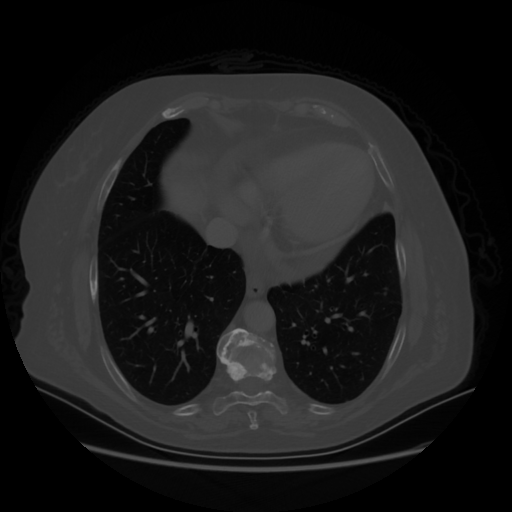

Original NATIVE CT scan (input)

No window - Raw intensity values

Lung window (WL -600, WW 1500 β†’ Low βˆ’1350, High +150)